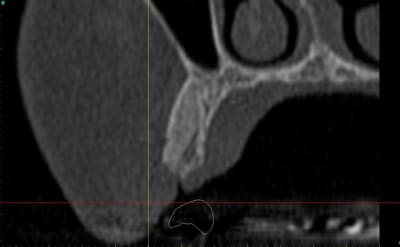

dentiste57 écrivait:

--------------------

> et là ?

> greffe selon ta méthode ?

Cross section dhvkc8 - Eugenol

3d dt3qom - Eugenol

Overview uqcp6u - Eugenol

S2y2o1v7q53ws4r5wy6ou8czrpom - Eugenol

pxav

01/05/2011 à 12h55

> dentiste57 écrivait:

> --------------------

> > et là ?

> > greffe selon ta méthode ?

expansion, c'est plus cool!